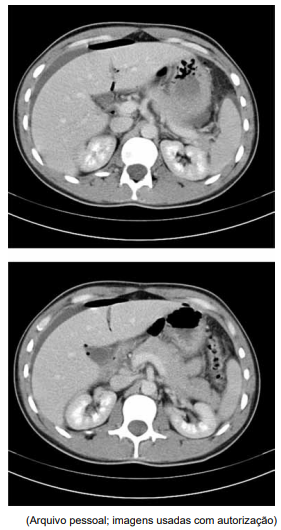

Ao exame físico, estava em regular estado geral e com fácies de dor, tendo apresentado vômito na admissão. A frequência cardíaca é de 125 bpm e a pressão arterial de 110 x 85 mmHg. Pouco colaborativo, não permite exame físico abdominal adequado por dor. Realizou o exame de imagem exibido a seguir e, após retornar do exame, evoluiu com rebaixamento do nível de consciência, hipotensão e má perfusão periférica.

Ao exame físico, estava em regular estado geral e com fácies de dor, tendo apresentado vômito na admissão. A frequência cardíaca é de 125 bpm e a pressão arterial de 110 x 85 mmHg. Pouco colaborativo, não permite exame físico abdominal adequado por dor. Realizou o exame de imagem exibido a seguir e, após retornar do exame, evoluiu com rebaixamento do nível de consciência, hipotensão e má perfusão periférica.